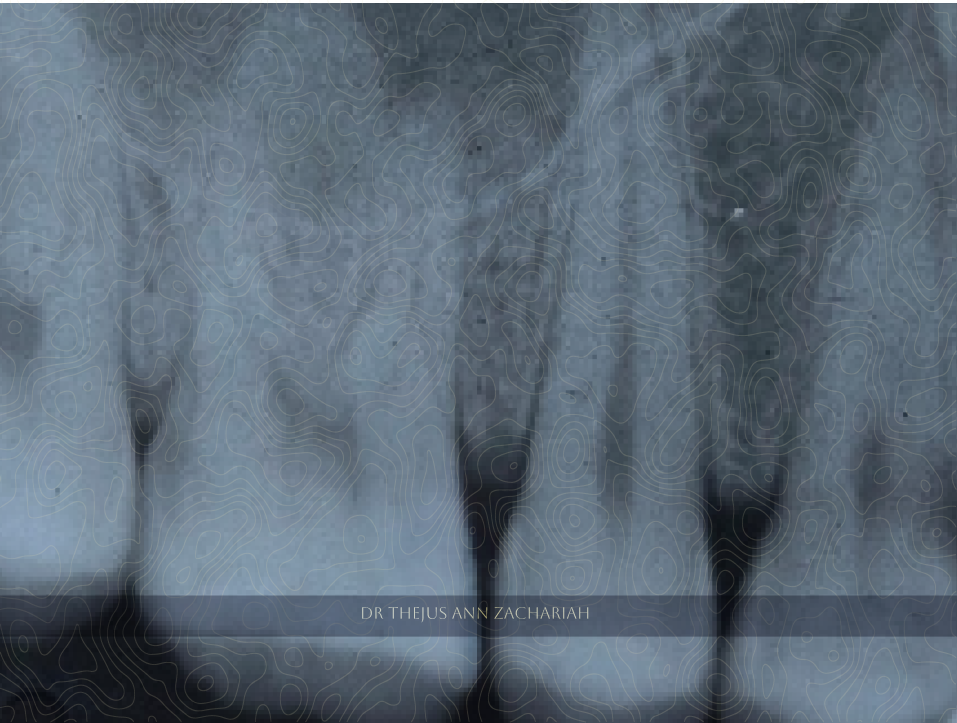

Pre & Post-Operative X Ray

alt text alt text